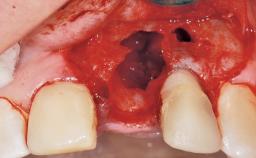

Immediate Flapless Placement of an Implant in a Maxillary Left Central Incisor Site

A 42-year-old female patient was referred to our clinic at the School of Dentistry of the University of São Paulo in November 2004, presenting a deficient restoration in the upper left central incisor. The clinical examination revealed no gingival retraction or any signs of gingival inflammation and, therefore, previous periodontal treatment was not considered. The patient presented a high lip line at full smile and a thin tissue biotype. This combination characterized a high-risk situation from an anatomic point of view, which required careful preoperative planning and cautious surgical execution.

Socket Morphology Single-root socket

Socket Integrity Sufficient, with intact bone walls

Bone Volume Sufficient, with intact walls